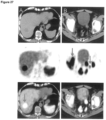

- Figure 21 demonstrates the maximum intensity projection (MIR) from PET of a subject with normal biodistribution (no tumor lesions detectable). Images were acquired 76 min post injection of 272 MBq 18F-labelled PSMA-SIFA3 (7). Figure 21 right demonstrates the maximum intensity projection (MIP) from PET of a subject with moderately advanced disease exhibiting multiple tumor lesions with high lesion-to-background ratio. Images were acquired 102 min post injection of 312 MBq 18F-labelled PSMA-SIFA3 (7).

- Imaging examples show favorable characteristics. Both small subcentimeter lesions and diffuse metastatic disease involving different tissue types are shown.

- Figure 26 shows: MIR (A) and transaxial images (B-D) of a 70 year old patient with biochemical recurrence 1.5 years after radical prostatectomy (Gleason 8, pT2c, pN1).

- a single prostate cancer typical lesion with 5 mm diameter in right pelvis with high uptake of 18F-labelled PSMA-SIFA3 (7) is present. Malignant nature of the lesion was verified by histopathology.

- Figure 27 shows: Set of images of an 80 year old patient with progressive advanced castration resistant prostate cancer (PSA 66.4 ng/ml). Images shows high uptake of 18F-labelled PSMA-SIFA3 (7) in different classes of prostate cancer lesions (local tumor, lymph node metastases, bone metastases, liver metastases). Lesions demonstrated are as small as 2 mm (arrows indicate representative, not all tumor lesions).

- Figure 28 shows proof of concept investigation of a 68 Ga-labelled SiFA substituted chelator-based PET tracer.